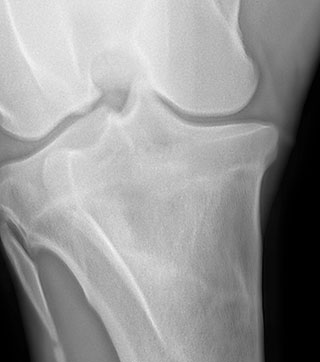

Radiología

Contamos con el equipo de radiología digital inalámbrico más avanzado del país, el cual permite obtener las mejores imágenes en el acto y compartirlas vía mail. Realiza radiografías de miembros, columna, cabeza, cuello y hombro.